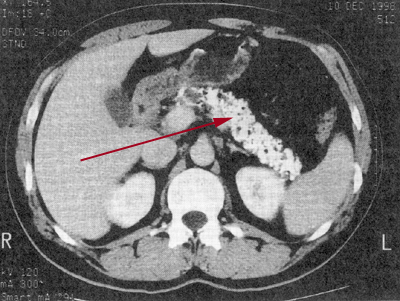

Oben: Das Bild der Computertomographie bzw. die Skizze zeigen einen deutlich erweiterten Pankreasgang im Körper der Bauchspeicheldrüse, mit Verkalkungen

Oben: Verkalkung (Pfeil) bei chronischer Pankreatitis.